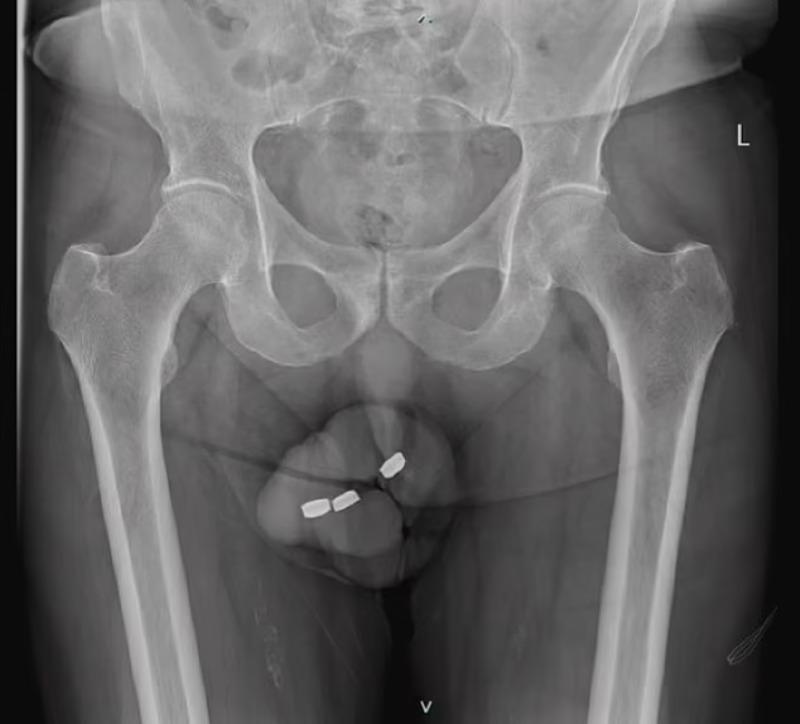

Người đàn ông này thú nhận với nhân viên y tế rằng anh ta đã tự chèn ba cục pin vào ống tiểu.

Bác sĩ cho biết, những viên pin nút mà người đàn ông chèn vào ống tiểu có đường kính khoảng 1,3 cm. Nhưng khi họ cố gắng lấy ra bằng kẹp y tế thì có những viên pin bị kẹp sâu hơn trong ống tiểu.